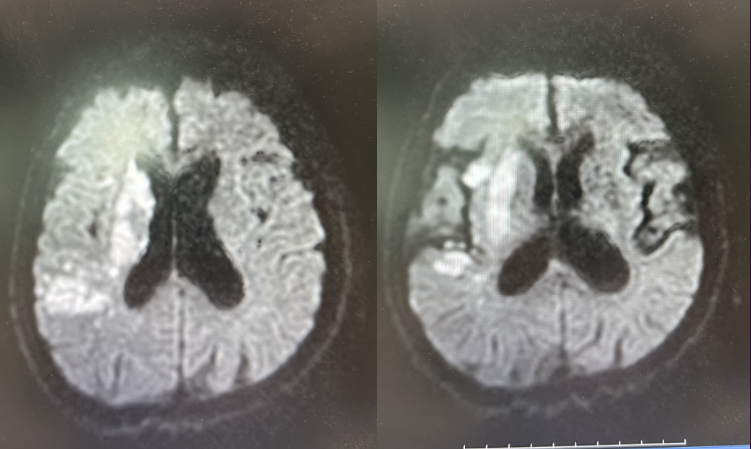

图二:颈内动脉球囊扩张+支架植入术后

术后次日复查CT,无颅内出血及造影剂滞留。TCD及颈动脉彩超提示右侧颈内动脉系统血供良好。

术后48小时查头颅核磁,提示右侧大脑半球大面积脑梗死,右侧大脑中动脉充盈良好。

图四:48小时头颅核磁+血管